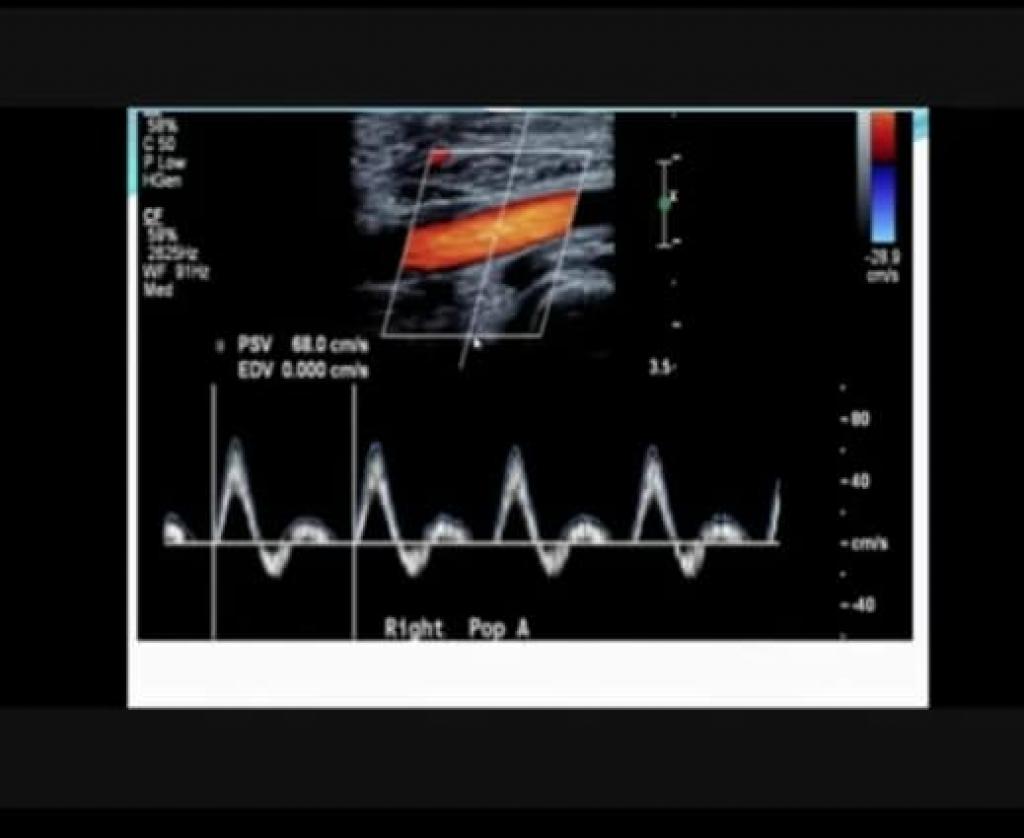

برعاية السيد رئيس جامعة الموصل الأستاذ الدكتور قصي كمال الدين الأحمدي و بإشراف السيدة عميد كلية العلوم الأستاذ المساعد الدكتورة هيام عادل إبراهيم الطائي أقام قسم الفيزياء الحياتية وعلى مدار ثلاثة أيام دورة التطبيقات الفيزيائية في المجالات الطبية و البايولوجية و بحضور السيد رئيس قسم الفيزياء الحياتية أ.م.د. مروان زهير الياس .شملت الدورة شرحاً وافياً عن مختلف التطبيقات الفيزيائية في المجال الطبي و البايولوجي من قبل الأساتذة المنظمين للدورة و هم كل من ( د. قصي خطاب عمر ) و ( د. إنعام أحمد حمزة ) .إذ استعرضوا مبادئها وأهم التطورات التي رافقت هذه التطبيقات خلال السنوات الأخيرة و حضر الدورة أساتذة وشخصيات علمية من داخل وخارج جامعة الموصل .